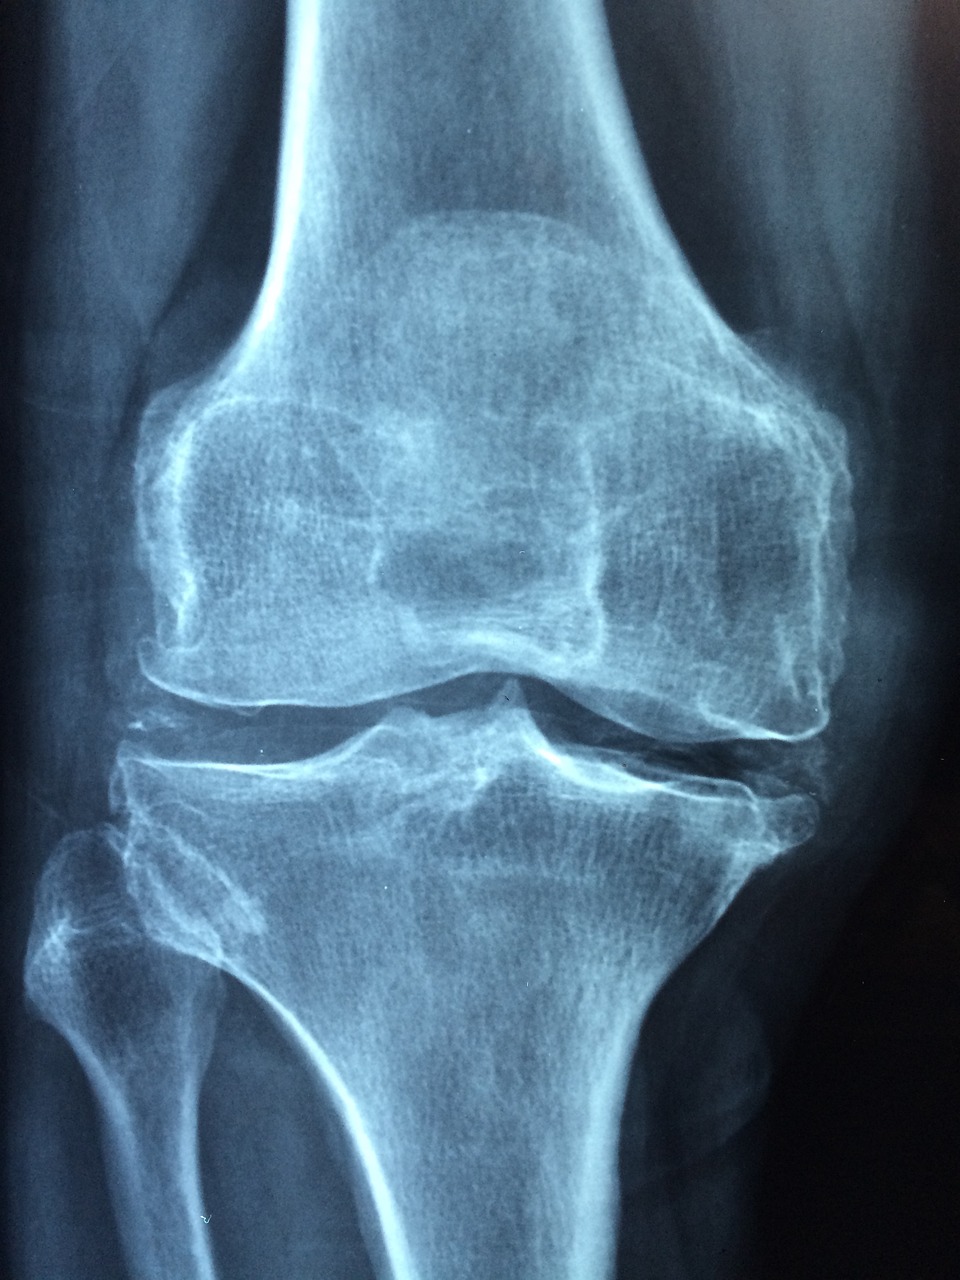

콘드로이친은 관절염 증상을 완화하는 데 도움을 줄 수 있어요.

관절 연골을 보호하고, 마찰을 줄이는 역할을 해요.

염증 반응을 억제해 통증을 줄이는 데에도 효과가 있어요.

특히 무릎, 손목, 허리 등 다양한 부위의 관절 통증 관리에 도움이 돼요.

몇몇 연구에서는 콘드로이친 복용이 퇴행성 관절염 진행을 늦춘다고 보고되었어요.